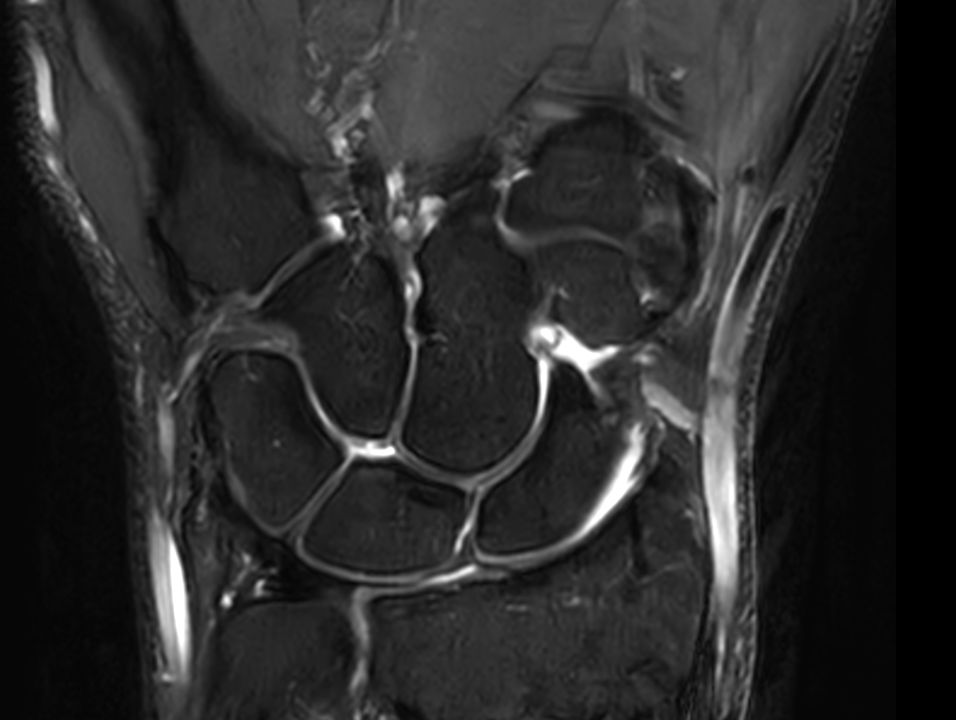

Coronal T2w TSE FatSat

Coronal T2w TSE FatSatSmartSpeed

Coronal T2w TSE FatSatSmartSpeed Resolution